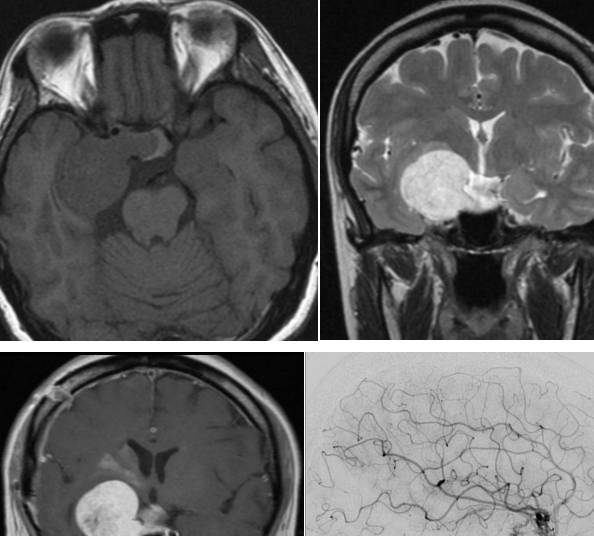

女,60岁,眶后头痛2月,视力下降伴复视4天。

脑寄生虫病、低灌注脑梗死、基底动脉尖综合征丨3分钟读片 ...

答案:颈内动脉-海绵窦瘘。狭义的颈内动脉海绵窦瘘(CCF)通常指的是颈内动脉海绵窦段的动脉壁或其分支发生破裂,以致与海绵窦之间形成异常的动静脉交通,而广义的CCF还包括海绵窦的硬脑膜动静脉瘘。Barrow等在1985提出了广义的CCF分型,分别为:A型,颈内动脉直接与海绵窦相交通;B型,颈内动脉分支与海绵窦相交通;C型颈外动脉分支与海绵窦相交通;D型即B+C,颈内和颈外动脉都通过其脑膜支与海绵窦相通,常有双侧同时供血。临床工作中,由于治疗理念和方法上存在区别,目前通常将BarrowA型单列为CCF,又称直接型颈动脉海绵窦瘘(狭义CCF),而B、C和D型统称为海绵窦硬脑膜动静脉瘘。CCF可分为外伤性和自发性。外伤性CCF较为常见,通常见于交通事故中伴有颅底骨折的外伤患者,颞骨和蝶骨的骨折碎片刺破海绵窦段颈内动脉壁,骨折片吸收后而出现CCF。因此CCF的症状通常发生于外伤后数周或数月。

CCF的症状与瘘口的流量以及引流方式有关。根据典型的病史及体征,CCF的临床诊断通常并无疑问,CTA/MRA有助于进一步明确诊断和鉴别诊断。DSA则是诊断的金标准,也为治疗提供了详尽的血管结构学和血流动力学信息。